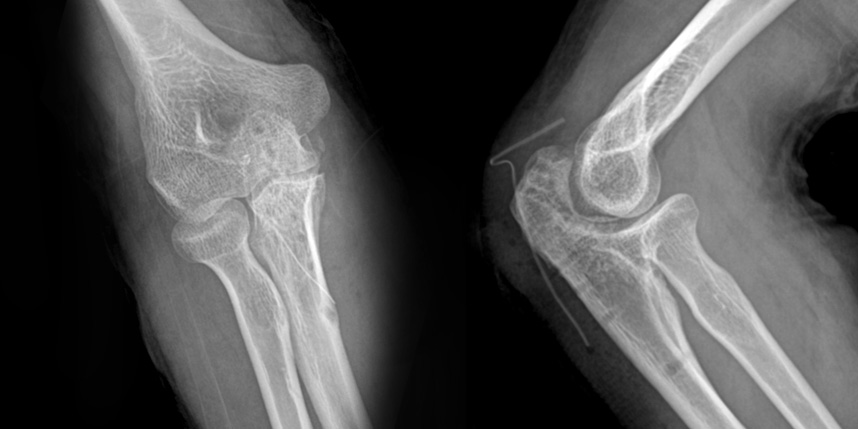

상완골 골절